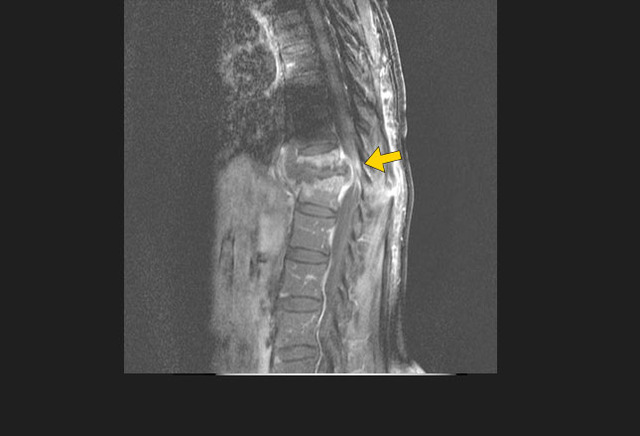

图6. 增强T1加权的磁共振矢状面图像展示了波特病的椎体受累表现

免疫系统受损的患者(例如HIV阳性患者)是发生肺外结核的高危人群。肺外结核可能侵犯多个器官或组织,包括心脏、肝脏、脾脏、眼、胃肠道、脑组织和脊椎。很多肺外结核患者胸部X线表现正常。

波特病(继发于结核血行播散的骨髓炎或椎间盘炎症)可能导致渐进性椎体塌陷和后凸畸形。